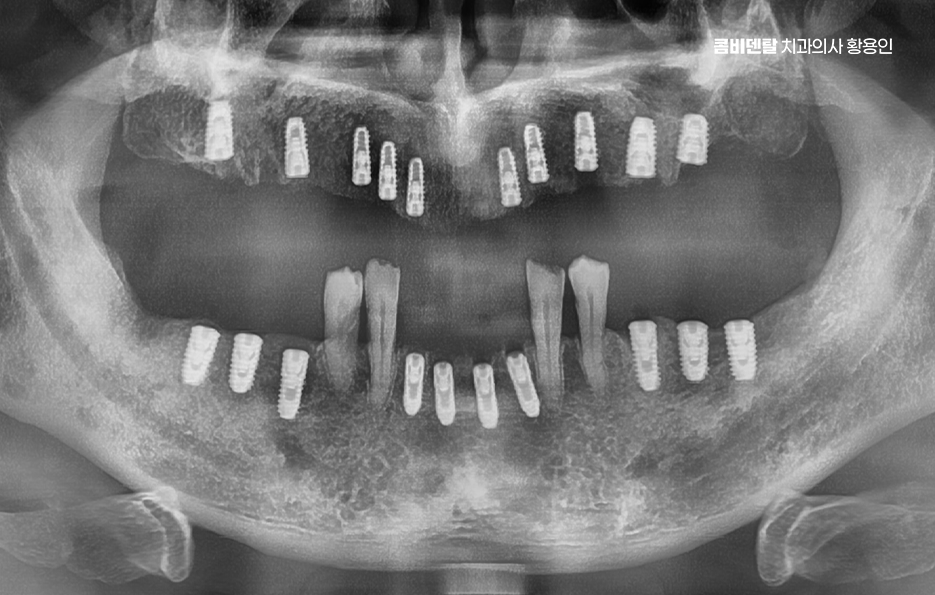

전체 임플란트를 한다고 해서 꼭 치아의 상실 개수만큼 1:1로 임플란트를 심는 건 아니며 보통 무치악인 경우에는 6개에서 8개 정도의 임플란트를 일정한 간격으로 심고, 그 위에 여러 개의 치아가 연결된 브릿지 형태의 보철물을 올리는 방식으로 치료를 하며 환자의 경제적인 부분 부터 잇몸 뼈의 상태에 따라 임플란트의 식립 개수는 다소 차이가 있어요

예를 들어 잇몸 뼈가 충분히 있는 경우에는 임플란트를 더 많이 심어서 지지력을 높이고, 잇몸 뼈가 많이 줄어든 경우에는 임플란트의 식립 개수를 최소화 하는 방식으로 치료 방법이 달라지는 것이며 경우에 따라서는 임플란트 틀니 처럼 임플란트와 틀니의 중간 지점의 선택지를 활용하는 경우도 있어요

특히 윗니 전체 임플란트 시에 보철물 제작은 환자의 얼굴 형태, 입술선, 웃을 때 노출되는 치아의 길이까지 고려해서 정교하게 디자인되어야 하며 특히 윗니는 발음과 표정에도 큰 영향을 주기 때문에, 단순히 기능적인 회복이 아니라 미소선과 조화로운 보철물 제작에서 중요하며 최근에는 디지털 스캔을 통해 보다 정교한 치료가 가능해지고 있었어요

윗니 전체 임플란트 치료에서 또 하나 주의할 점은 정기적인 관리로 임플란트는 자연치아처럼 신경이 없기 때문에 문제 발생 초기에 통증이 없을 수 있지만 임플란트 주위염 같은 염증이 생기면 잇몸뼈가 녹아내리기 때문에 정기적인 스케일링, 구강위생 관리, 그리고 올바른 칫솔질 습관이 필수이며 특히 전체 임플란트의 경우는 하나만 문제가 생겨도 전체 보철물에 영향을 줄 수 있기 때문에, 더 세심한 관리가 필요하고 재수술에 대한 부담이 그만큼 커지기 때문에 치료와 동시에 장기적인 사후관리의 중요성이 더욱 높다는 점을 잘 고려하여 치과 역시도 오래 함께할 곳을 꼼꼼하게 잘 선택하시길 바라고 있어요